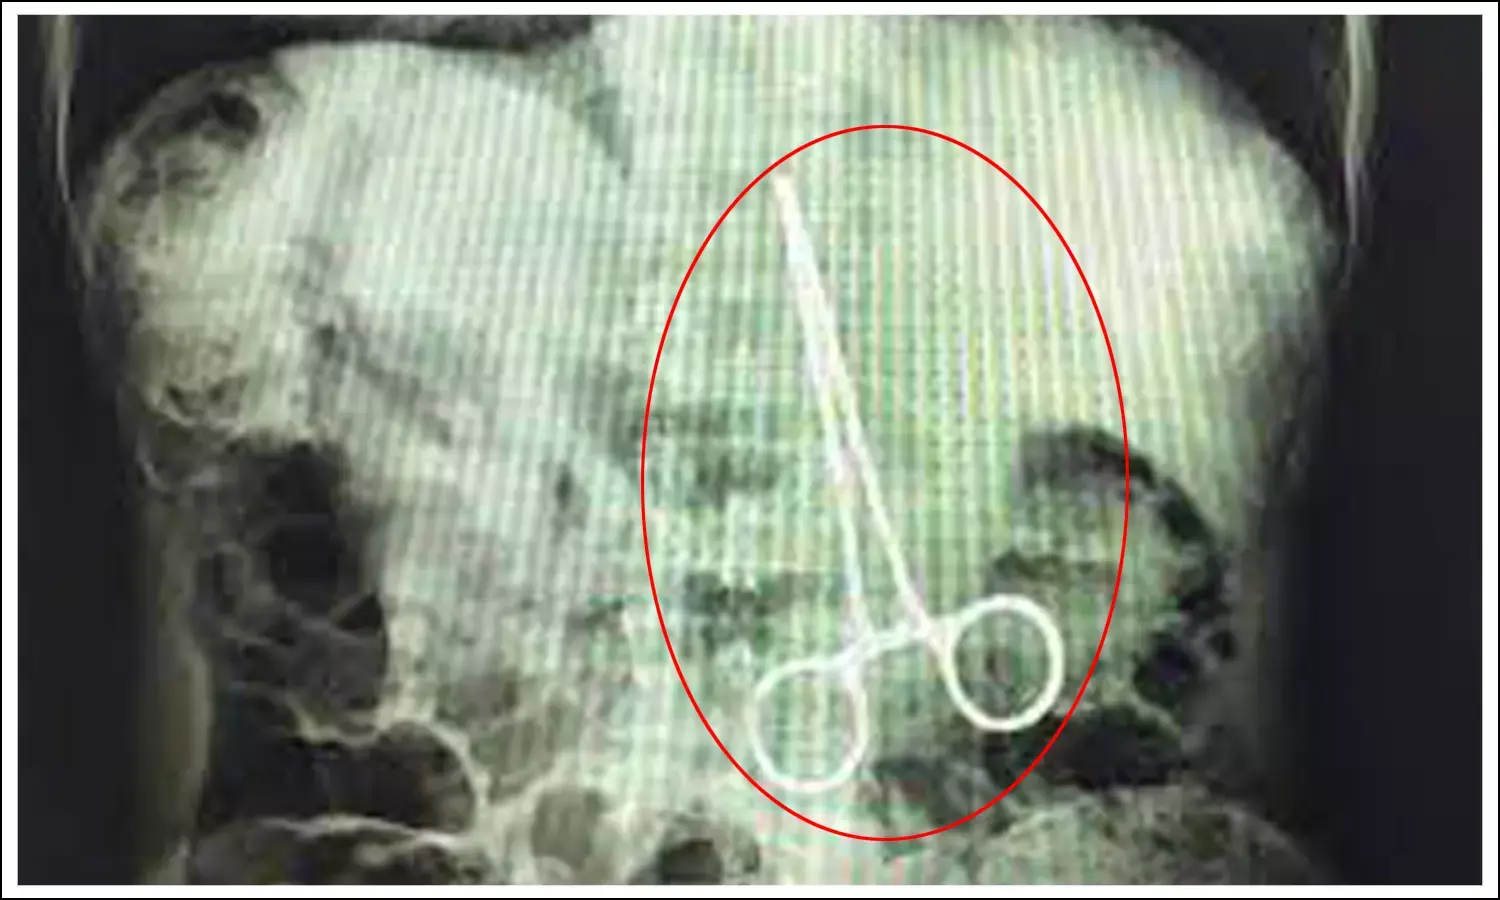

ఆగస్టు 10వ తేదిన ఏలూరు నుంచి స్వప్న అనే మహిళను విజయవాడలోని ప్రభుత్వ ఆసుపత్రికి తీసుకొచ్చారని తెలిపారు. అయితే సర్జికల్ ఫోర్‌సెప్ (కత్తెర)ను ఆమె కడుపులోనే వదిలేశాని పేర్కొన్నారు. ఆ కత్తెర పొడవు రెండు ఇంచుల వరకు ఉందని వైద్యులు చెబుతున్నారు. కడుపులో వదిలేసిన కత్తెర పేగకి అతుక్కుపోవడంతో ఆమెకు కడుపు నొప్పి తీవ్రమైంది. దీంతో కత్తెర అతుక్కుపోయిన పేగు కుళ్లిపోయిందని అన్నారు. , ప్రస్తుతం ఆ కుళ్లిపోయిన పేగును తీసేసి చికిత్స నిర్వహిస్తున్నామని వైద్యులు తెలిపారు. దీంతో మహిళ ఆరోగ్య పరిస్థితి ప్రస్తుతం నిలకడగా ఉందని విజయవాడ ప్రభుత్వ ఆసుపత్రి వైద్యులు ప్రభాకర్‌, సర్జరీ విభాగాధిపతి అప్పారావులు వెల్లడించారు.

వివరాల్లోకి వెళితే..పెదపాడు మండలం ఎస్.కొత్తపల్లి అనే గ్రామానికి చెందిన స్వప్న ప్రసవం కోసం ఏప్రిల్ 19వ తేదిన బోధనాసుపత్రిలో చేరింది. అయితే గర్భిణీతో ఉన్న ఆమెకు ఆపరేషన్‌ చేసి బిడ్డను బయటకు తీశారు. అయితే మహిళకు తీవ్ర కడుపు నొప్పి రావడంతో ఆమె పరిస్థితి ఆందోళకరంగా మారిందని వైద్యులు తెలిపారు. అయితే వైద్యులు ఆమెకు ఆపరేషన్‌ చేసిన తర్వాత డిశ్చార్జి చేశారు. ఇంటికి వెళ్లిపోయిన స్వప్నకు తరచుగా కడుపు నొప్పి వచ్చేది. ఇలా నొప్పులు వచ్చినప్పుడు సాధారణంగా వచ్చే నొప్పులు ఏమో అనుకుని మందులు వాడేది. అయితే ఆగస్టు 8వ తేదిన స్వప్నకు విపరీతంగా కడుపు నొప్పి వచ్చింది. దీంతో తిరిగి ఏలూరులోని బోధనాసుపత్రికే వెళ్లింది. కానీ అక్కడ వైద్యులు ఆమెకు పరీక్షలు చేసిన తర్వాత విజయవాడలోని ఆసుపత్రికి సిఫార్సు చేశారు. దీంతో అక్కడ ఆమెను పరీక్షించగా అసలు విషయం బయటకు వచ్చింది. స్వప్న కడుపులో కత్తెర ఉన్నట్లు ఎక్స్‌రే ద్వారా బయటపడింది.